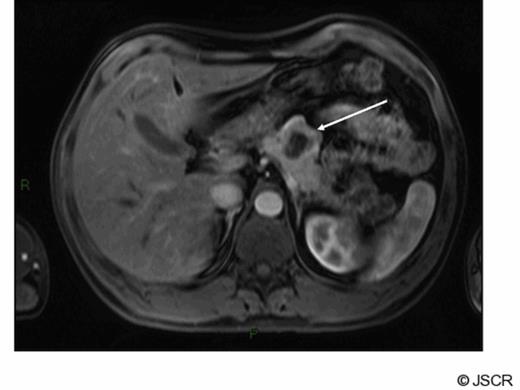

At operation this was a well defined lesion with no evidence of intra-abdominal metastasis. There was no evidence of pancreatitis and the remaining gland appeared normal. Pathology confirmed a single well demarcated mass that histologically was a well-differentiated endocrine tumour. No lymphovascular space invasion was noted and complete excision was achieved with good margins. The tumour measured 39mm, the Ki-67 proliferation index was less than 2% and together with a mitotic count of less than 1 in 10 high powered fields confirmed this was, according to the WHO classification, a well-differentiated (grade 1) endocrine tumour of uncertain behaviour. No cytological atypia or necrosis was identified. The patient made an uneventful post operative recovery however at follow up 6 months later he complained of recurrent sweats and hot flushes. CT scan showed apparent evidence of recurrence of tumour at the site of the previous resection margin in a similar location to the original primary tumour with additional abnormal soft tissue adjacent to the greater curvature of the stomach consistent with local or nodal recurrence. No liver or lung metastases were identified. These findings were confirmed on MRI scan (fig 2).

Arterial phase gadolinium enhanced MRI demonstrating lesion reported as being consistent with recurrent neuroendocrine cancer (arrow).